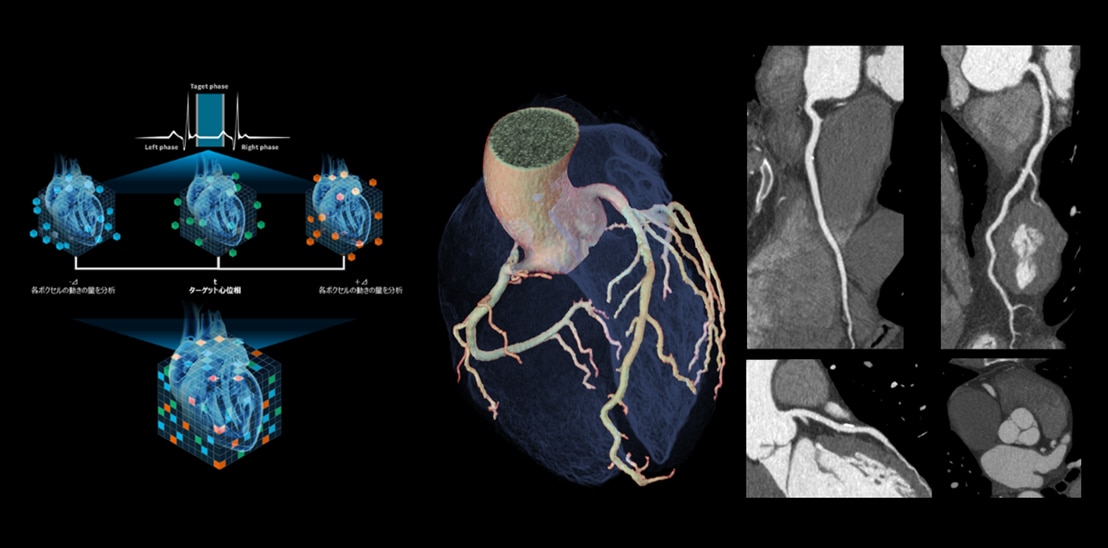

160mmワイドカバレッジCTの有用性が最も活かされる領域の一つとして、循環器領域・心臓CTが挙げられます。近年では、循環器臨床における治療、特に経カテーテル的治療の進歩により、冠動脈の評価だけでなく、弁や心房等、冠動脈以外の術前心臓CT評価のニーズも増えており、従来以上に心臓全体でのモーションアーチファクトの低減が重要となっています。このことからGEヘルスケアでは独自の動態ベクトル解析を用いたモーション抑制アルゴリズムSnapShot Freeze2.0(SSF2.0)により、心臓全体のモーションアーチファクトの抑制に取り組んできました。TAVI、経皮的僧帽弁クリップ術、更には三尖弁においても径カテーテル的治療の広がりが期待されていますが、三尖弁は薄く、また距離・位置的にも経食道心エコーでの評価が難しいケースがあります。Revolution Apex Eliteでは最速0.23秒回転を実現し、SSF2.0と組み合わせることで他モダリティでも評価が難しい領域の画像化も期待でき、これら技術が開胸を行わない非侵襲的治療の安全実施に貢献します。

左 SnapShot Freeze2.0の概念図

ターゲット心位相とその前後の心位相の合計3心位相のフェーズデータを用いて、心臓を構成する各ボクセルの動態を3次元的にベクトル解析し、変化量をフィードバックし静止画像を生成

右 70kV, 0.23秒/回転で撮影した心臓CT画像